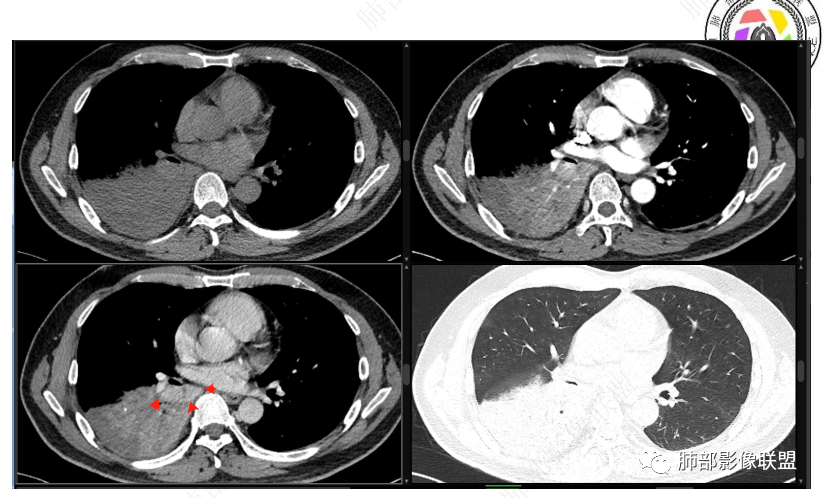

右下叶支气管狹窄,内见高密度强化结节,远端大片不张实变,实变内可见多发粘液拴,整体观察实变似有见缝就针的感觉,综和分析考虑粘液表皮样癌,其次考虑类癌

中央型肿瘤pk周围型肿瘤  。壮年男性,热咳一周伴气喘,中性白细胞升高,临床是个感染过程。支持中央型病变的证据:1  肺门明显强化结节 2 横s征  3 支气管粘液栓  4 主支气管变窄,似见冰山征      支持周围型病变:1 按叶段塑形  2 血管造影征  3 病灶内弥漫高强化  4 周围伴磨玻璃灶,但境界不清继发感染?误吸?综合 中央型肿瘤可能大:类癌》鳞癌

右肺下叶不张,右下肺门区高强化结节,似乎呈冰山征,首先考虑类癌可能

右下肺门似见一结节影,明显强化,远端支气管黏液栓,右肺下叶不张,考虑类癌,次之黏液表皮样癌 腺样囊腺癌

首先血管未见明显侵犯、移位,提示病灶:炎性;肿瘤:外朝内——含粘液类腺癌(肺门淋巴结转移),腔内肿瘤(鳞癌、腺癌、类癌、小细胞、粘液表皮等)

腔内肿瘤,远端堵塞

如果重建确定在腔内,那就鉴别黏表

我觉得粘液表皮可能要放前面

腔内

按理类癌远端密度不会这么低

中心性起源:主要位于段及段以上支气管,多为气管、支气管腔内软组织结节及肿块,卵圆形或分叶状,沿支气管壁生长,最长径与支气管走行长径平行,与近心端支气管管腔呈钝角,支气管内可见“空气新月征”。

周围型MEC少见,且CT表现不具特征性,周围型结节或肿块,可出现分叶、毛刺等恶性征象,坏死、空洞较常见CT平扫多为欠均匀的低-中等密度,增强扫描后病灶以轻-中度不均匀强化为主。

肿块内钙化:MEC较其他类型肺癌钙化率高,约50%病例中可见斑点或颗粒状钙化。钙化可能与病程较长,局部血供少致营养不良性钙化有关,肿瘤支气管远端可出现阻塞性肺炎及肺不张征象。

鉴别诊断:

1.肺腺样囊性癌:是下呼吸道最常见涎腺肿瘤,占气管肿瘤的30-40%起源,相对局限于气管侧壁及后壁腺体丰富区域。临床分期高,容易复发和转移,多预后不良。好发部位以气管、主支气管为主,沿管壁浸润性生长引起长段管腔狭窄较MEC常见。在CT上多呈均匀低密度,瘤内钙化少见,增强后强化不明显。

2.肺类癌:源于支气管粘膜Kulchtsky细胞,恶性程度低,淋巴结转移少见,平均发病年龄较MEC偏大,为45-55岁类癌常分泌血清素、缓激肽,患者常有哮鸣样支气管痉挛、阵发性心动过速、水样腹泻、皮肤潮红等副肿瘤综合征表现CT上类癌出现钙化的比例小,空洞少见,富含血供而明显均匀强化。